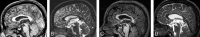

Materials and methods: Brain MR images of 100 healthy young volunteers were randomly selected from our International Consortium for Brain Mapping project data base. Cysts were detected as circular areas of isointensity relative to CSF on both 3D gradient-echo T1-weighted and 2D fast spin-echo T2-weighted images. The inner diameters of all visualized pineal cysts were measured, and a criterion of 2.0 mm of the largest inner cross-sectional diameter was used to categorize cysts as being either small cystic changes (<2.0-mm diameter) or pineal cysts (>2.0-mm diameter).

Results: Twenty-three percent (23/100) of the volunteers had pineal cysts with a mean largest inner cross-sectional diameter of 4.3 mm (range, 2-14 mm); 13% (13/100) demonstrated cystic changes involving the pineal gland with the largest inner cross-sectional diameter of less than 2.0 mm. There was a slight female predominance. Two subjects with long-term follow-up scans showed no symptoms or changes in the size of their pineal cysts.